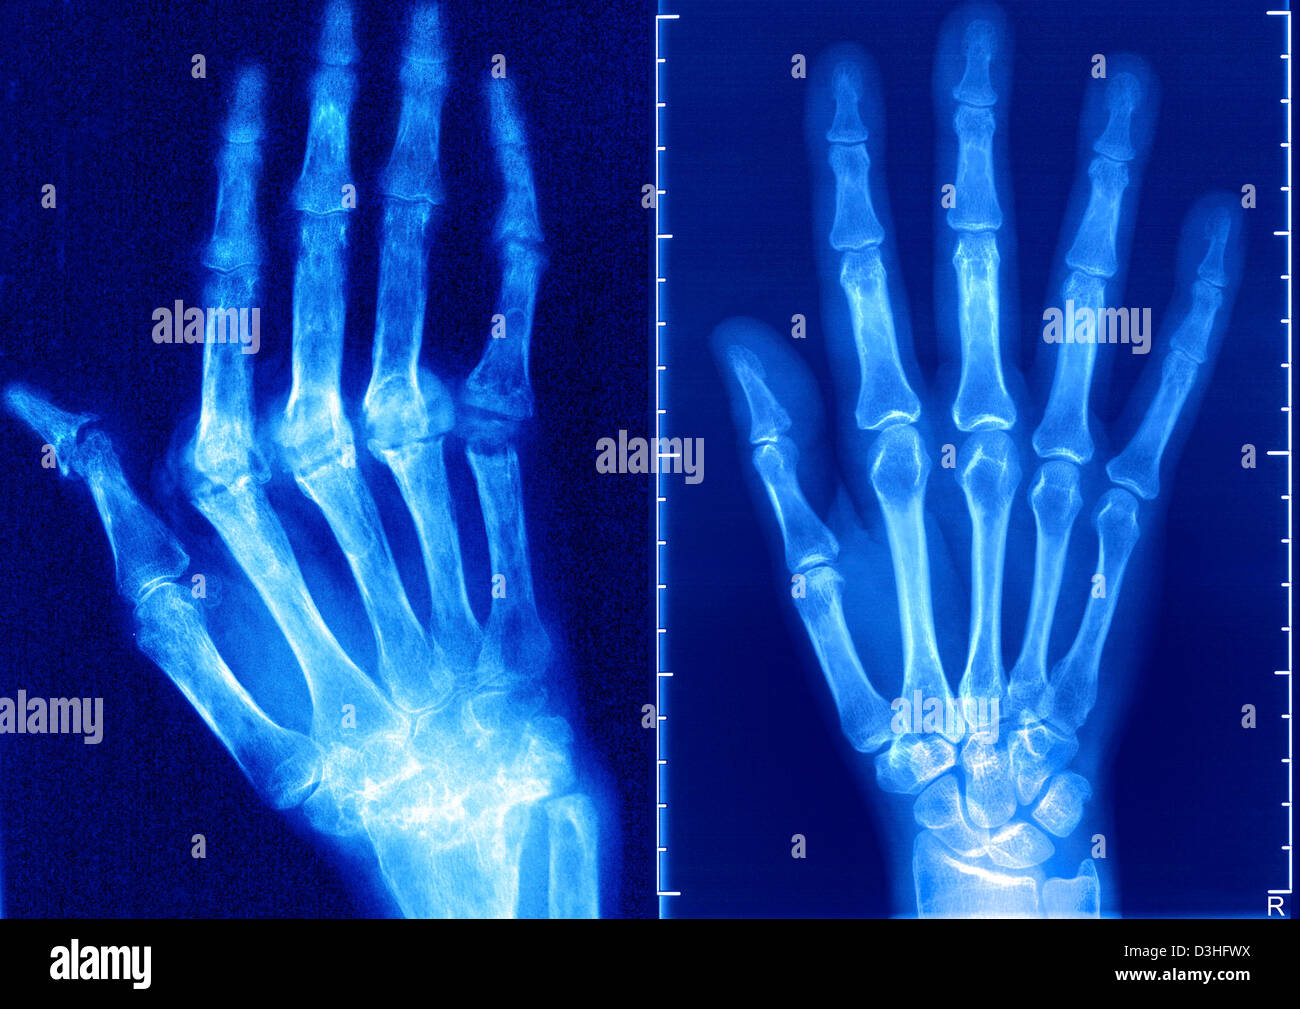

Arthritis X-Ray . To get pictures of the affected joint, your doctor might recommend: Plain radiograph is the most commonly used modality in assessment of osteoarthritis due to its availability and low cost. At hss, this view is usually obtained with the patient standing and bearing weight on the joint. It can detect bony features of.